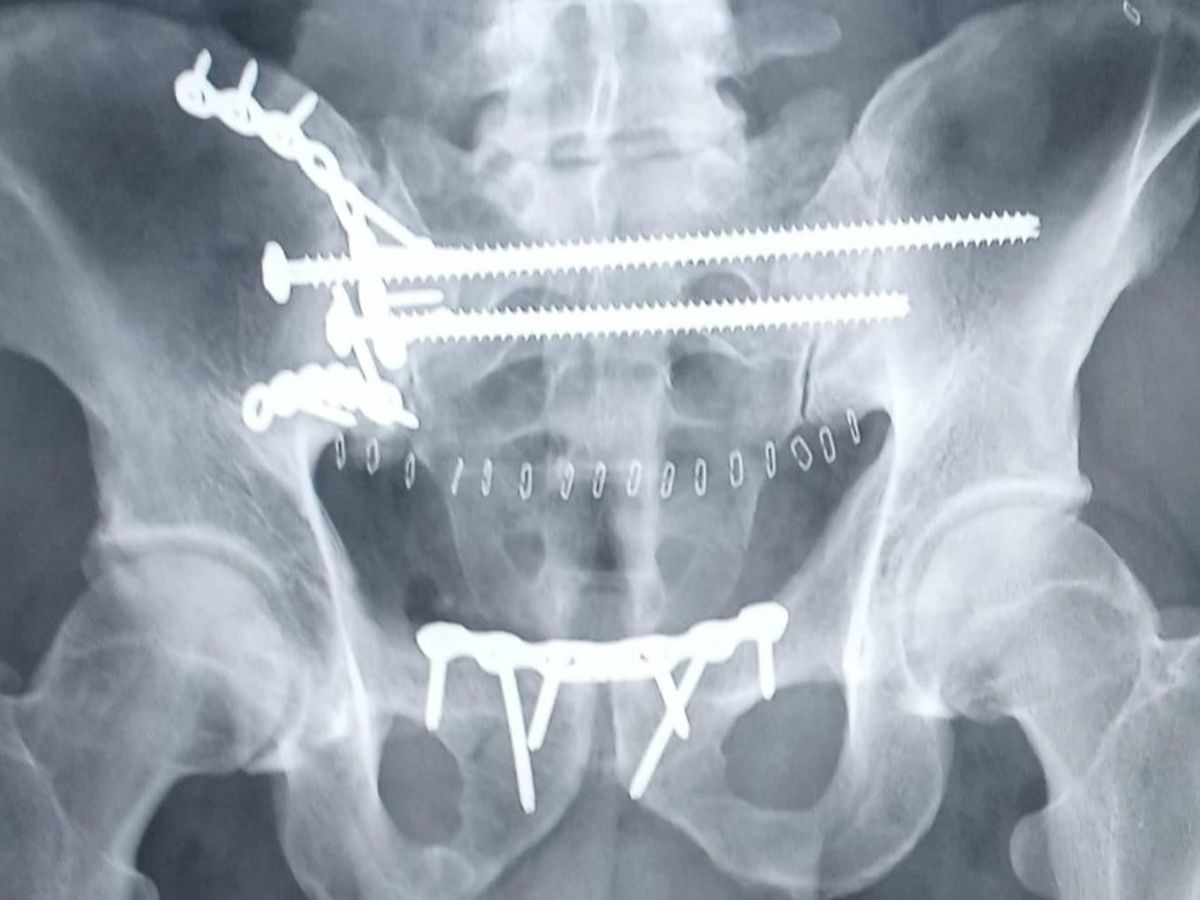

It's with a heavy heart that I am here to inform you about my brother Joel who was severely injured in a terrible motorcycle accident. As some of you may know, last Thursday as Joel was leaving work, he lost control and crashed into a solid brick pillar. He was immediately taken to the hospital and admitted into the ICU. He endured 5 broken ribs which caused his lung to collapse. He had to be put on a ventilator to breathe. The next major issue the doctors found was that he was suffering from the most severely shattered pelvis that the surgeon had ever seen. There was damage found to his kidney, bowel, and he had a laceration on his liver.

Well that was not the worst. Later that Thursday night, he had internal bleeding and was rushed to have emergency surgery to remove his spleen that nearly ruptured and a portion of his large intestine was removed as well. The next hurdle was surgery on his pelvis. He was given a total of 5 units of blood with both surgeries. We have also been informed that he has a few broken vertebrae, bone fragments in his shoulder (which will need surgery as well) and even though he is off of the ventilator, he is in severe pain.